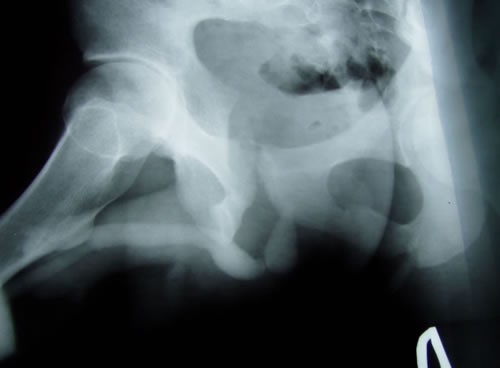

Рентгенография:

1. Восходящая цистография: